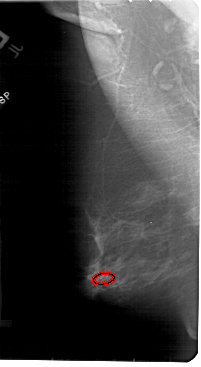

FILE: A_1840_1.LEFT_MLO.OVERLAY

TOTAL_ABNORMALITIES 1

ABNORMALITY 1

LESION_TYPE CALCIFICATION TYPE PLEOMORPHIC DISTRIBUTION CLUSTERED

ASSESSMENT 4

SUBTLETY 2

PATHOLOGY BENIGN

TOTAL_OUTLINES 1

BOUNDARY